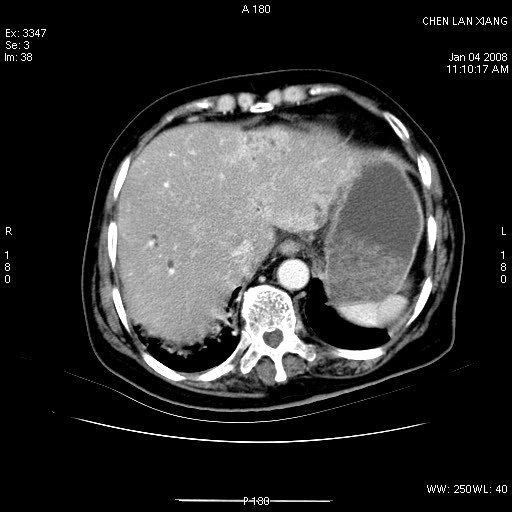

女,76岁,腹痛3-4天,b超示:肝内实性肿物,胆囊强回声,胆总管扩张.

1 胆总管末端结石伴肝内胆管结石,肝内外胆管扩张。2 胆囊扩大,胆囊壁不规则增厚,内见软组织密度影。考虑:慢性胆囊炎,不除外胆囊癌!

胆囊密度增高,增强后周边肝组织及胆囊窝下部周边软组织延时性不规则强化.然胆囊壁未见明显不规则增厚及肿块.左侧肝内胆管及胆总管下段结石伴胆系扩张.

考虑;胆囊炎(黄色肉芽肿性胆囊炎?),左侧肝内胆管及胆总管下段结石.

标题: 肝右叶病灶

胆囊癌侵犯肝右叶?

1)胆囊癌伴肝脏转移。2)胆总管下端结石、肝内胆管结石伴肝内外胆管扩张。